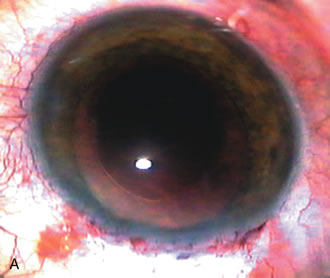

Fig. 5. Anterior chamber angle changes associated with lens extraction and PCIOL This 65-year-old Vietnamese woman has a long-standing history of chronic angle-closure glaucoma treated with laser peripheral iridectomy. The optic nerve demonstrated mild glaucomatous damage and IOP was moderately controlled on two antiglaucoma medications. The cataract was removed through temporal clear corneal phacoemulsification with foldable acrylic IOL. A. Symptomatic cataract in narrow-angle glaucoma eye with patent iridectomy. B. Intraoperative goniophotograph showing crowding of angle with increasing narrowness due to phacomorphic component. C. Intraoperative photograph showing temporal clear corneal approach with IOL in the capsular bag. D. Intraoperative goniophotograph demonstrating deepening of chamber angle following lens extraction. Proposed theories for IOP reduction following lens extraction with complete wound closure:

CATARACT EXTRACTION ALONE REDUCES IOP IN MOST EYES WITH ANGLE-CLOSURE GLAUCOMA

Uncomplicated cataract extraction substantially reduces IOP, along with the number of postoperative glaucoma medications in eyes with angle-closure glaucoma.146,147 When preoperative gonioscopy reveals PAS, along with adjacent areas of appositional closure, lens extraction alone in select cases may be a reasonable alternative to filtration surgery.148,149 Phacomorphic angle-closure disease due to enlargement of the lens with progressive angle crowding is eliminated following lens extraction. The width and depth of the anterior chamber angle in eyes with angle-closure glaucoma increases significantly after cataract extraction with IOL implantation and becomes similar to open-angle glaucoma and normal eyes.150,151 (Fig. 5). Combining phacoemulsification, IOL implantation, and limited goniosynechialysis is effective in the treatment of cataract and chronic angle-closure glaucoma.152 Phacoemulsification with implantation of a foldable IOL is more effective in reducing IOP and improving visual acuity than surgical peripheral iridectomy in eyes with acute angle-closure glaucoma.153